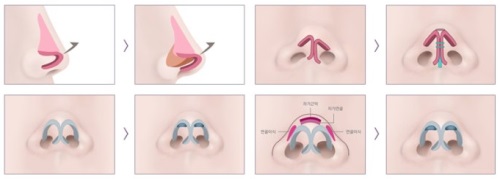

张医生拿个小探头在我鼻梁上扫了扫,说:“你这是假体层次放浅了才透光,鼻头歪是因为缝合时固定点没对齐,不用重做假体,把假体往深了调,再重新固定鼻头就行,还能保留你之前的鼻型基础,修复更快。”没有夸大结果,全是实实在在的分析。